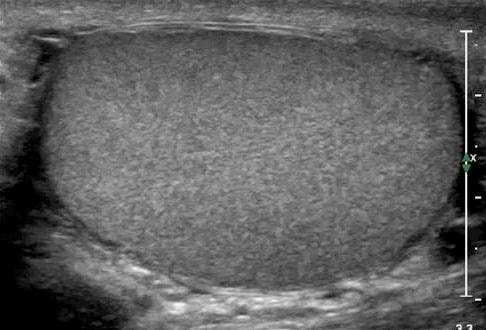

Προληπτική Εξέταση των Παθήσεων του Όσχεου

Παθήσεις του όσχεου: υπογονιμότητα, καλοήθεις παθήσεις και καρκίνος των όρχεων. Ο ρόλος του Υπερηχογραφήματος και του Τriplex - έγχρωμου Doppler Υπερηχογραφήματος στην πρόληψη και την διάγνωση...